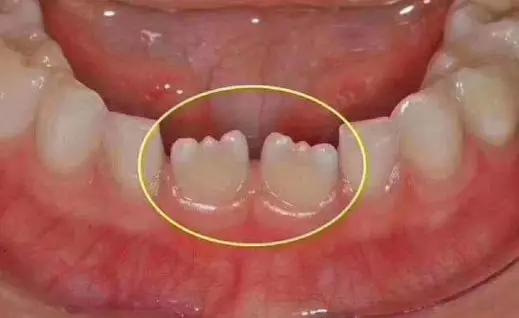

发育正常的上下门牙、侧切牙刚萌出时切端都呈锯齿状,医生将锯齿称为牙齿的发育结节,它属于牙齿的解剖形态,锯齿随着进食的磨耗会逐渐磨平。

因为牙齿的发育是由几个部分融合成的,我们称之为发育叶,新长出的牙齿发育叶之间融合的地方短,尖端长,牙齿就会呈现锯齿状。但随着牙齿发挥咀嚼功能,牙齿慢慢被磨耗,尖端的地方就被磨平了,也不再呈现锯齿状了,牙齿的咬合端就会变齐。